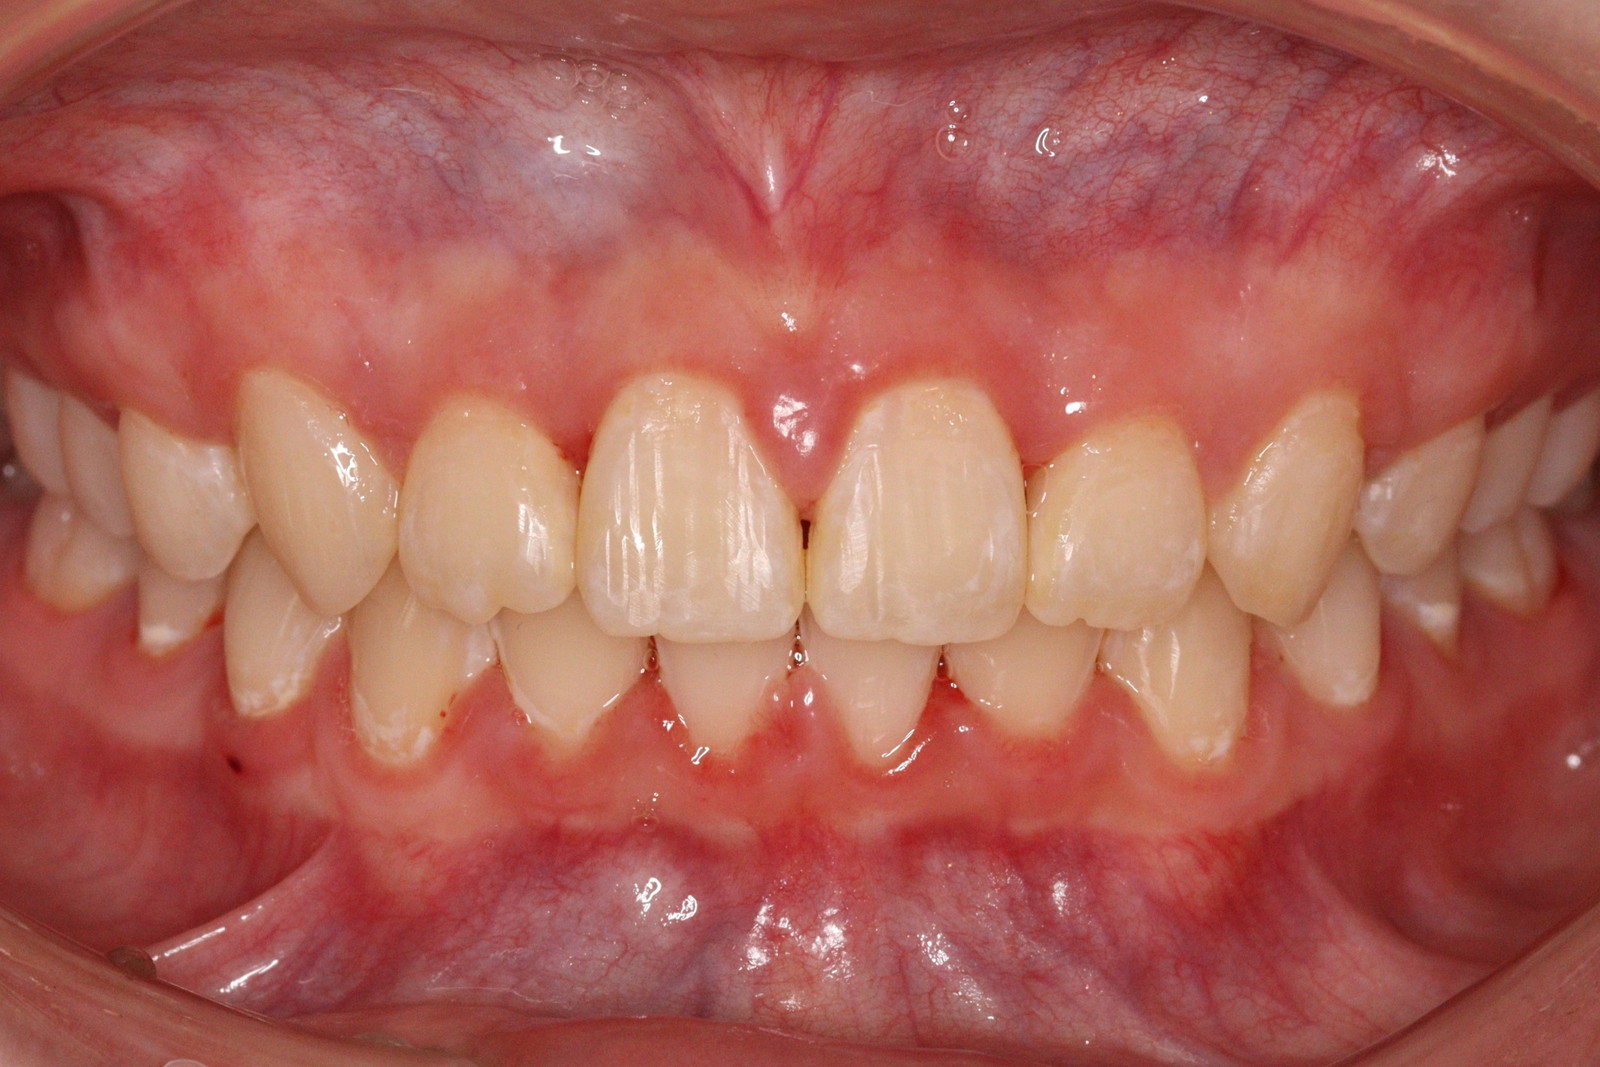

問診を行い、お口の悩みや希望を確認します。レントゲン撮影や口腔内写真の撮影など、必要に応じた精密検査を行います。

検査結果に基づき、現在の状態と治療計画(期間や費用含む)についてご説明します。